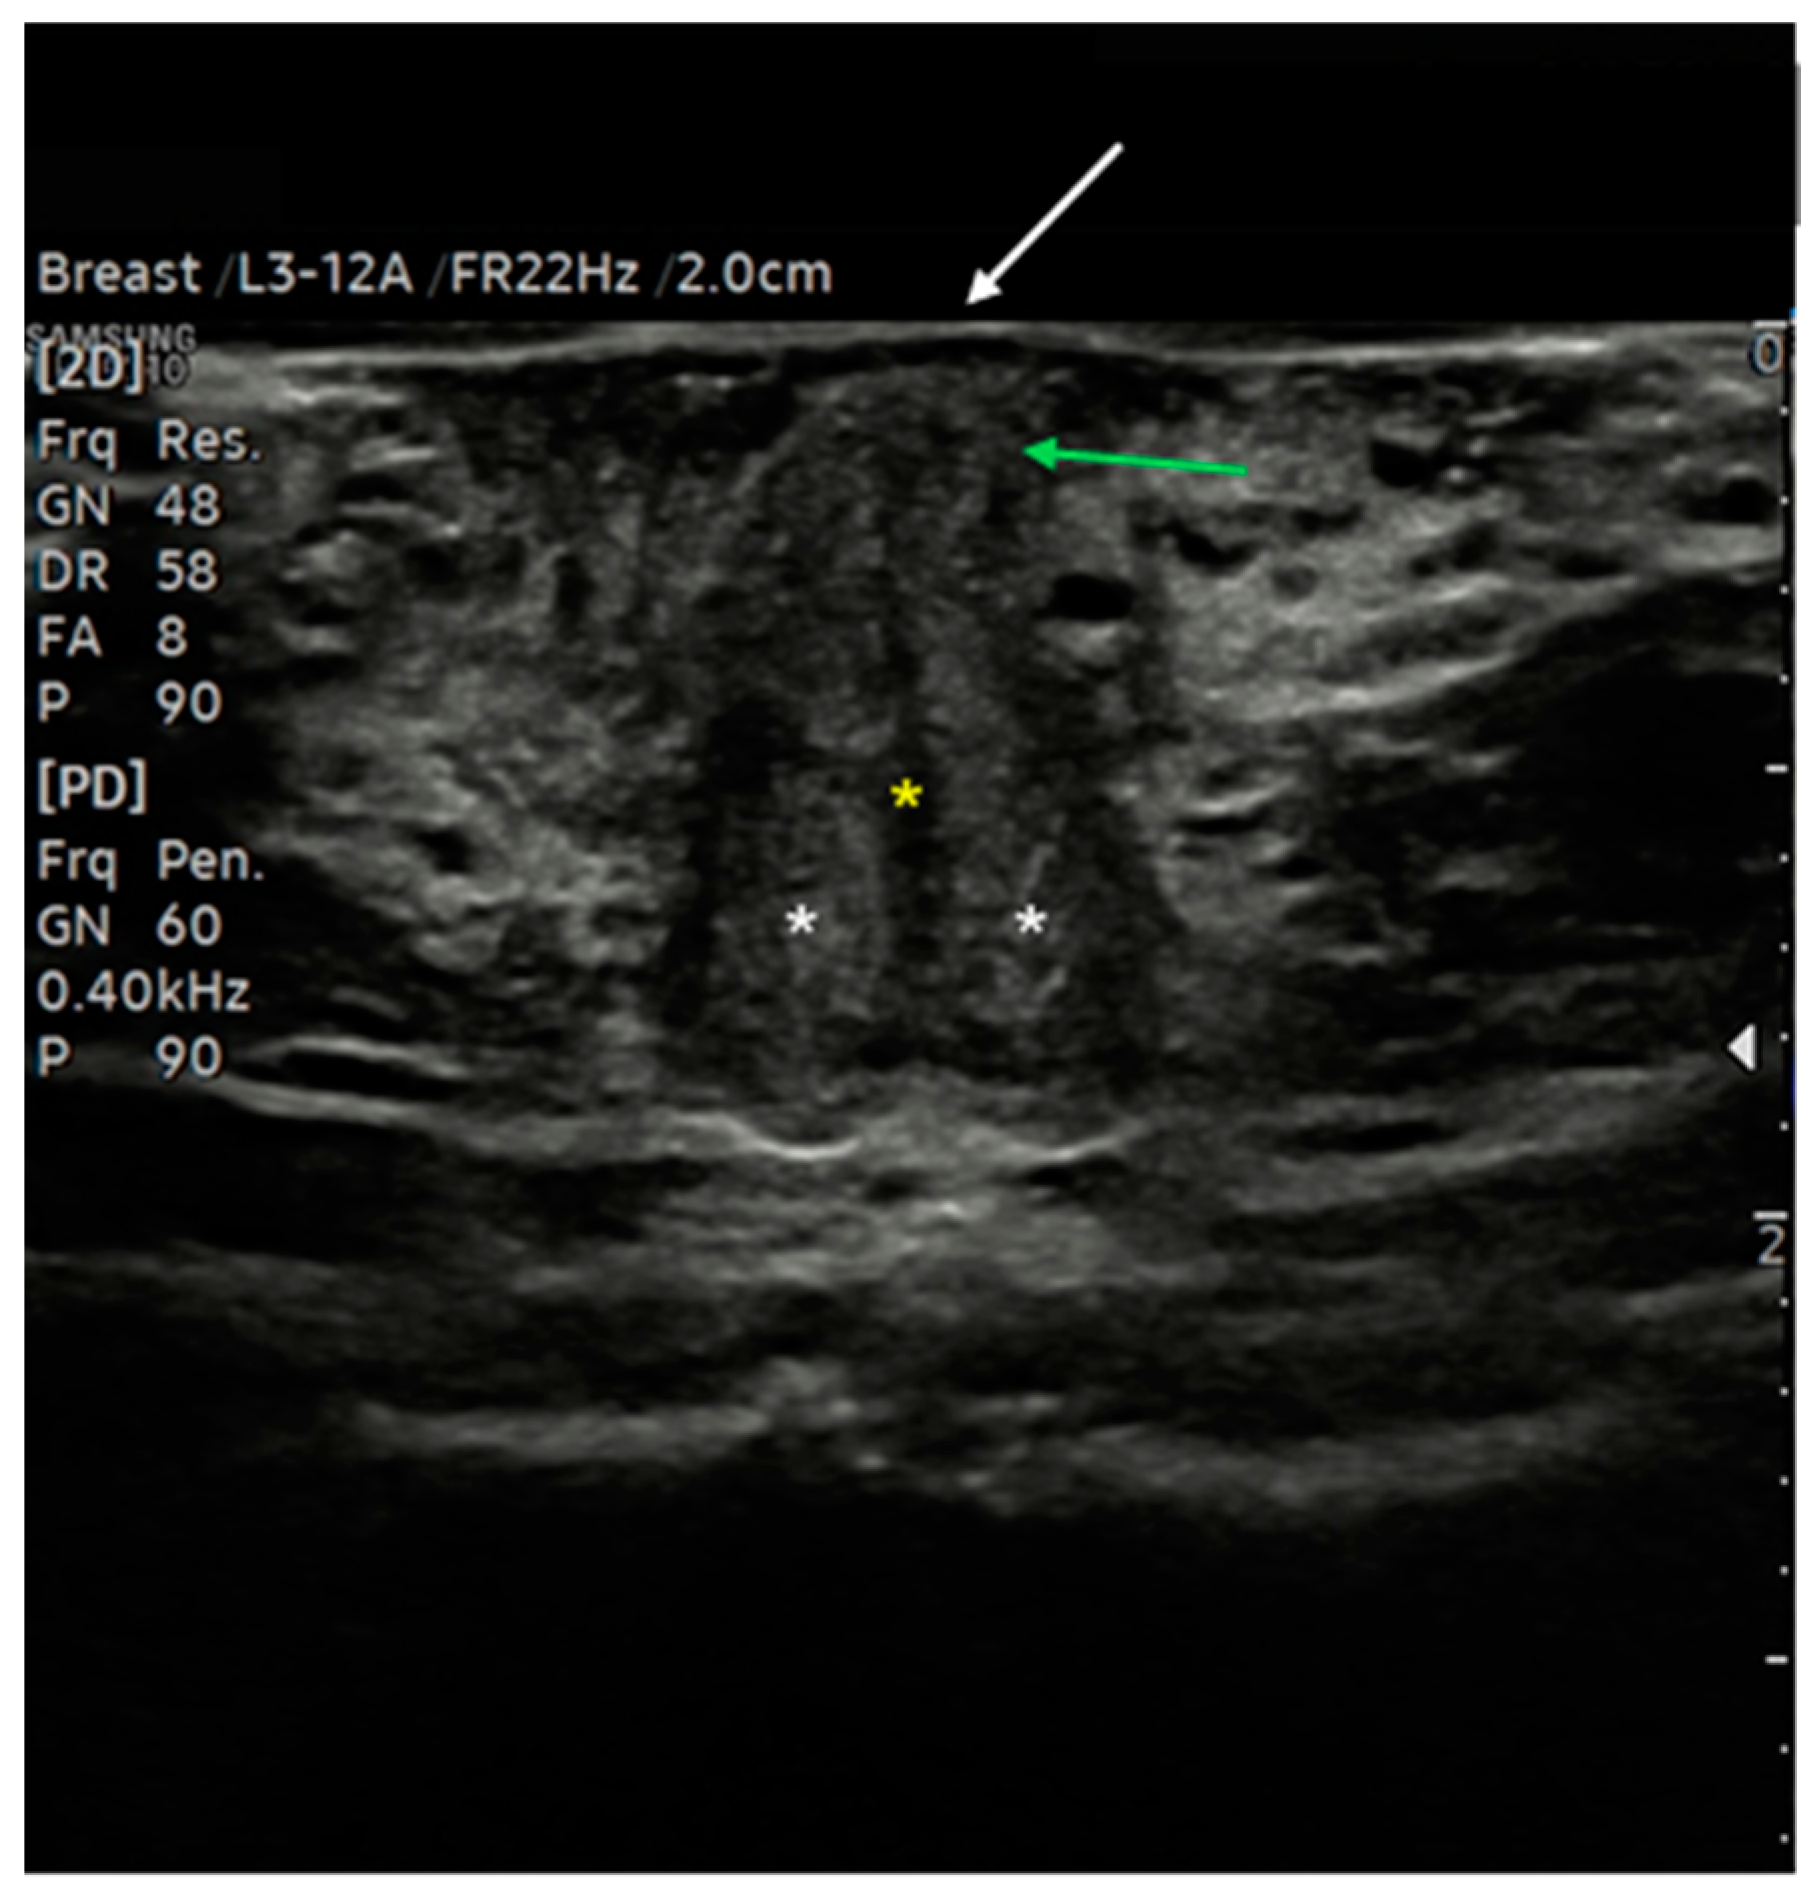

7.3. Malignant Vulvar Lesions

- Measurement from the adjacent most superficial dermal papilla to the deepest point of invasion

- Measurement from the basement membrane of the deepest adjacent dysplastic (tumor-free) rete ridge to the deepest point of invasion, which should be the technique of choice. Because epidermal ridges cannot be distinguished on ultrasonography, our suggestion is to take the lower hyperechogenic line of the epidermal layer as a reference (Figure 10).